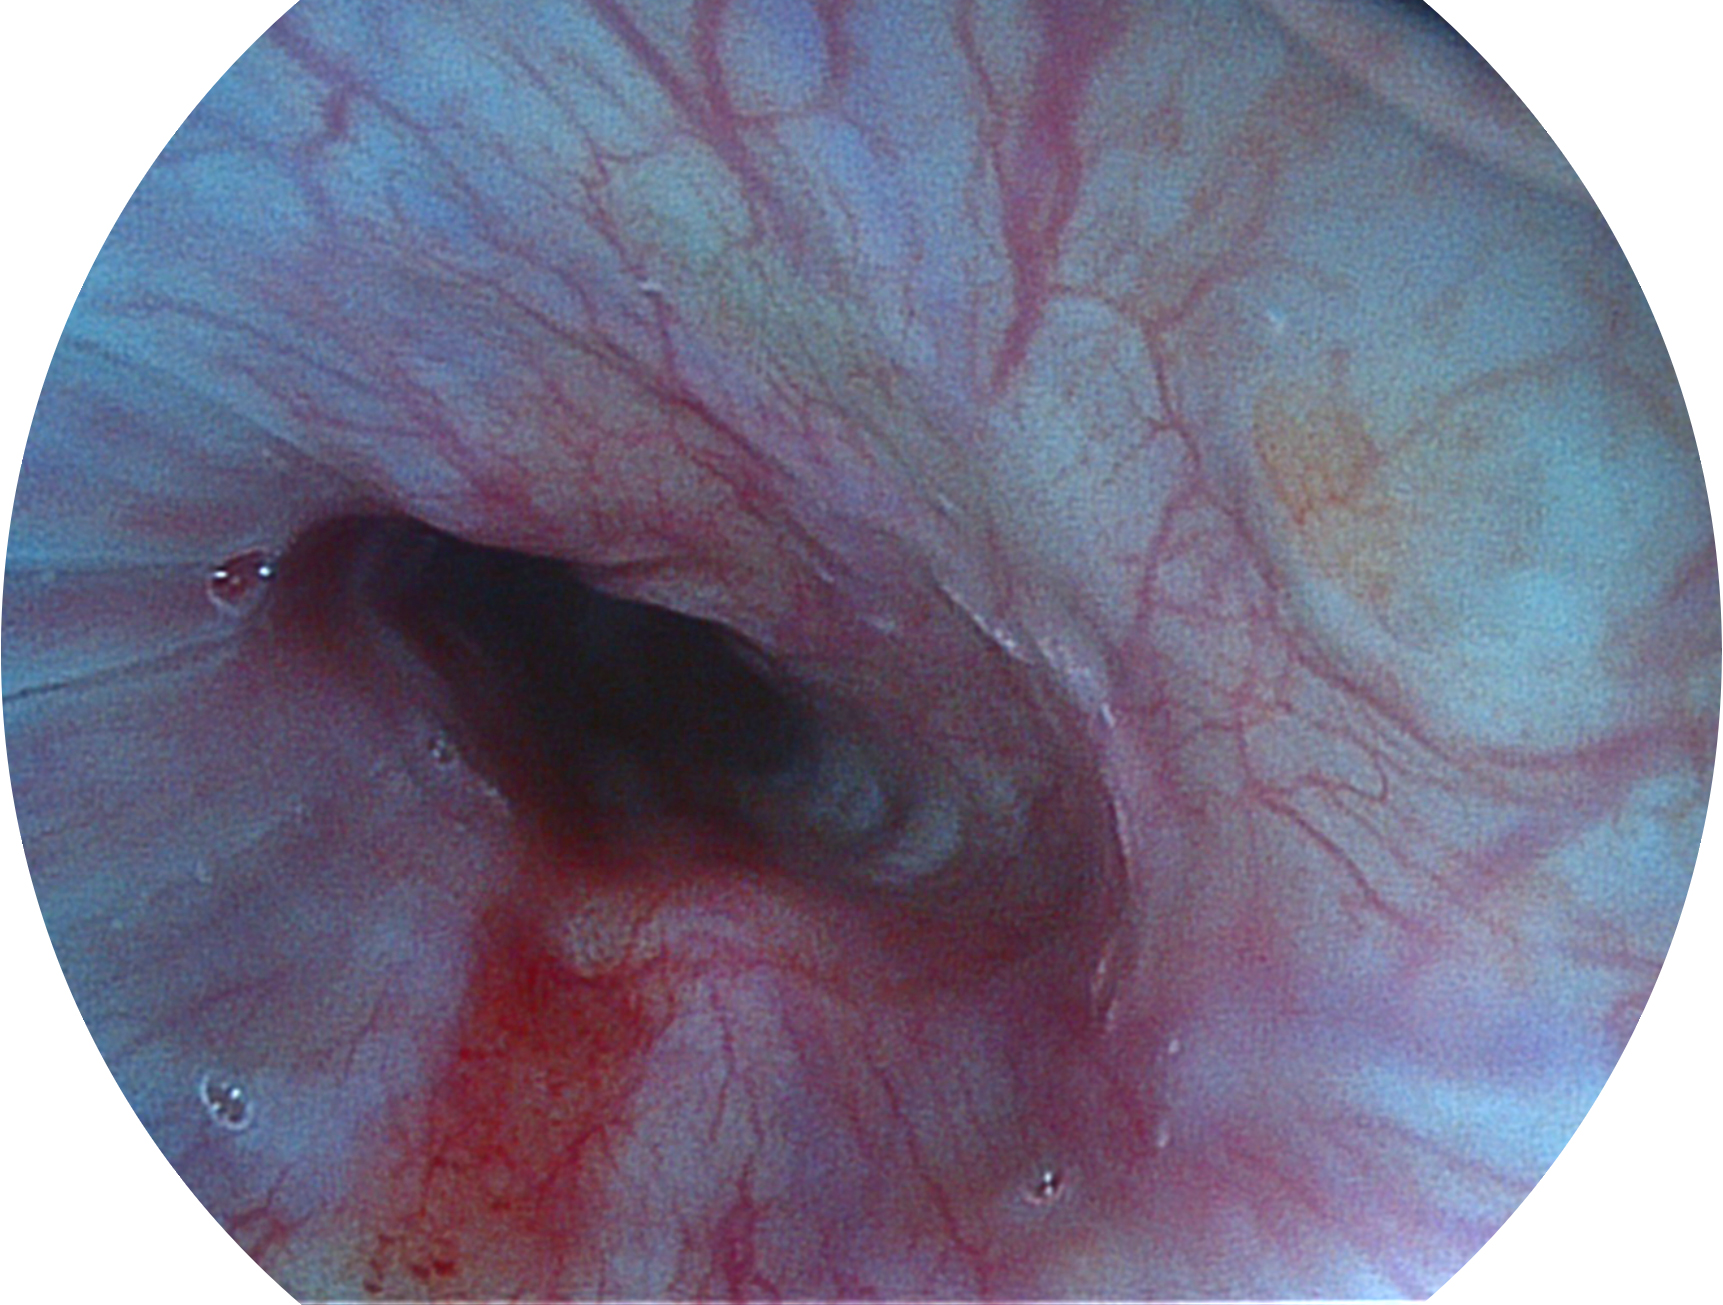

竞技宝(JJB)官方网站新开发的内镜染色技术,主要是基于多波长LED 光源的开发,VLS-55Q 四波长LED 光源是由四个不同颜色的LED光按照相应照明模式所规定的特定发光比例进行合束后形成,合束后形成的照明光的光谱由红光、绿光、蓝光及蓝紫光这四个不同的波段范围构成。具有更高光谱自由度,通过光谱比例的控制,实现了聚谱成像技术,英文全称为“Spectral Focused Imaging, SFI”,缩写为“SFI”和光电复合染色成像技术,英文全称为“Versatile Intelligent Staining Technology, VIST”,缩写为“VIST”。